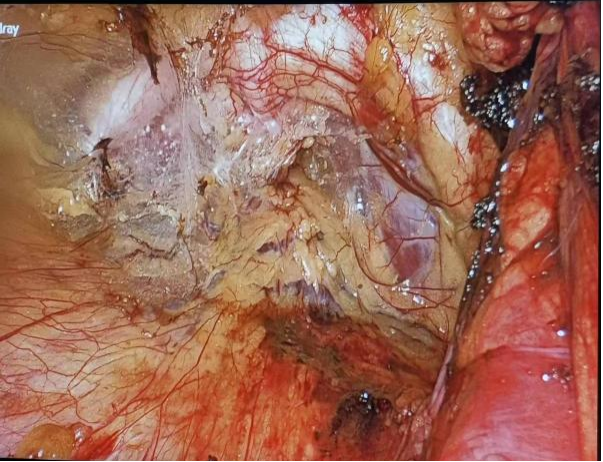

图2 TEP术式腹膜前间隙游离